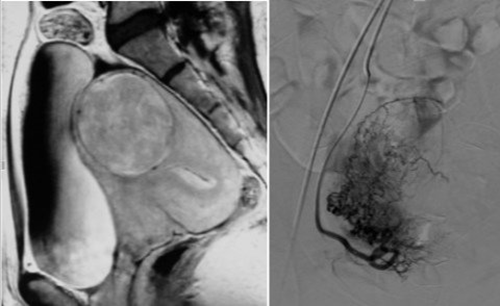

朱金虎主任表示,随着医学的进步,子宫腺肌症的治疗现在已经有多种方法,通常分为药物治疗与手术治疗。药物治疗适合症状轻微者,可通过皮下及肌肉注射药物,打针后上曼月乐环,症状缓解后再取环备孕;手术治疗中的微创介入治疗是需保留生育功能,以及维持女性社会心理完整(不少女性对切除子宫怀有抵触心理)的重症患者的优选,所谓介入治疗就是利用影像学技术进行子宫动脉栓塞处理,或使用消融电极经腹部插入子宫病变区,从而使病灶坏死,同时保留子宫,保障生育功能,术后极少有复发情况。

子宫肌瘤栓塞术影像

张女士的丈夫听闻广州市红十字会医院妇科主任医师朱金虎具有丰富的妇科治疗经验,便带张女士前来求医,朱金虎主任分析病情及听取张女士诉求后,建议张女士采用消融介入术治疗子宫腺肌症,经过MRI评估其子宫与肠管关系后,为张女士顺利实施了子宫腺肌症消融术。术后张女士的痛经症状已经消失,其爱人也愉快告诉朱金虎主任他们在考虑二胎的事宜了。